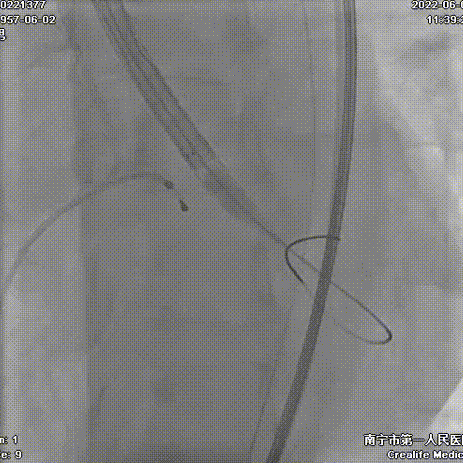

手术过程:

导丝跨瓣

Snare协助输送器跨瓣

本例手术为重度钙化二叶式病变重度主动脉瓣狭窄TAVR手术,团块状钙化挤压存在移位瓣周漏风险,术前手术团队对患者进行了全面细致的评估,确定假体瓣膜锚定区域范围,制定术前释放策略。球囊第一次通过困难,刘主任当机立断,采用外周小球囊预扩策略,再上20mm主动脉球囊充分预扩。通过球扩预判,果断采取snare辅助输送器顺利跨瓣。